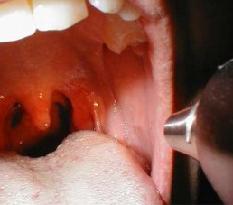

Диагностика включает в себя проведение посева на бактерии, а также, забор анализа крови, с помощью которых медики выявляют бактерию стафилококка. Чтобы определить чувствительность стафилококка к антибактериальным препаратам доктор проводит дополнительный тест.

Перед тем, как лечить стафилококк в горле, необходимо, чтобы учитывалось наличие индивидуальной непереносимости компонентов лекарства, поэтому для каждого пациента должен подбираться особый комплекс лечения. Дозировка также устанавливается лечащим врач в зависимости и она зависит от возрастной и весовой категории.